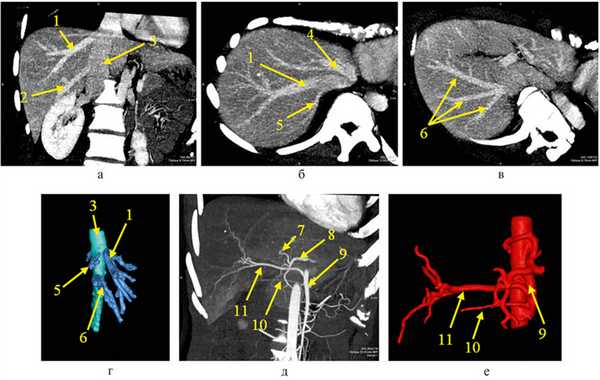

По данным компьютерной томографии: печень обычной формы. Кранио-каудальный размер правой доли — 150 мм. Объем паренхимы печени — 896 мл, объем правой доли — 596 мл. Объем остающейся левой доли печени (futureremnantliver — FRL) составил 33,5% к общему объему паренхимы печени. Индекс плотности паренхимы составил 10 ед., данных за стеатоз не получено. Паренхима равномерно накапливает контраст, без очаговых изменений. Внутри- и внепеченочные желчные протоки не расширены. Желчный пузырь не увеличен, без рентгенконтрастных включений. Левая печеночная артерия отходит от чревного ствола, питает сегменты S4a, b. Сегменты S2, S3 снабжаются ветвью левой желудочной артерии. Правая печеночная артерия отходит от верхней брыжеечной артерии, имеет диаметр 3 мм. Пузырная артерия, диаметром 1,5 мм отходит от верхней брыжеечной артерии дистальнее устья правой печеночной артерии (рис. 1).

Рис. 1. Компьютерная томография печени, венозная фаза (а—в). 3D-моделирование эфферентных сосудов правой доли печени. Боковая проекция. Вид справа (г). Компьютерная томография печени, артериальная фаза (д). 3D-моделирование афферентных сосудов печени (е). 1 — правая печеночная вена; 2 — правая нижняя печеночная вена; 3 — нижняя полая вена; 4 — левая и средняя печеночные вены, совместно впадающие в нижнюю полую вену; 5 — правая верхняя печеночная вена (отток от S7 печени); 6 — три правые нижние печеночные вены (отток от S5, S6, S7 печени); 7 — левая печеночная артерия; 8 — левая желудочная артерия; 9 — верхняя брыжеечная артерия; 10 — пузырная артерия (отходит от верхней брыжеечной артерии); 11 — правая печеночная артерия (отходит от верхней брыжеечной артерии).

Портальная система равномерно контрастирована, имеет место бифуркация ствола порты, поперечный размер портальной вены — 10 мм. Левая и средняя печеночная вены совместно впадают в нижнюю полую вену. В левую печеночную вену впадают две ветви, дренирующие S8 диаметром около 3 мм, одна из которых впадает в среднюю печеночную вену рядом с кавальными воротами, а также две ветви от S5, также имеющие диаметр около 3 мм. Диаметр средней печеночной вены — 7 мм. Правая печеночная вена имеет диаметр 9 мм, впадает в нижнюю полую вену на расстоянии 9 мм от средней печеночной вены. От сегмента S7 на уровне кавальных ворот, в нижнюю полую вену впадает ветвь диаметром 4 мм. От сегментов S7, S5, S6 в нижнюю полую вену, чуть выше уровня портальных ворот, рядом впадают три дополнительные ветви печеночных вен диаметром 4, 7 и 8 мм (см. рис. 1). Патологии органов брюшной полости и забрюшинного пространства не выявлено.